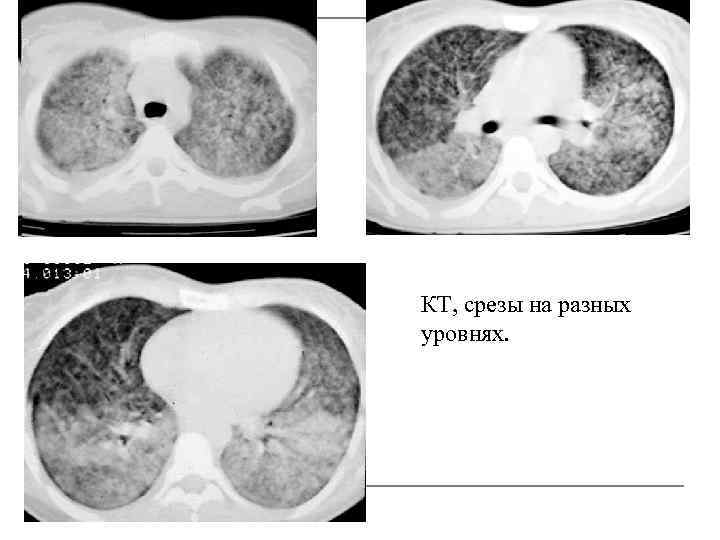

КТ, срезы на разных уровнях.

Высокоразрешающая КТ. Острый гематогенно-диссеминиро ванный туберкулез. Мономорфные мелкие очаги, расположены хаотично в обоих легких вне связи с интерстициальными структурами

Подострый гематогенно-диссеминированный туберкулез легких, высокоразрешающая КТ. Мелкоочаговая двухсторонняя диссеминация, хаотичное расположение очагов. В верхней доле левого легкого более крупные перибронхиальные очаги